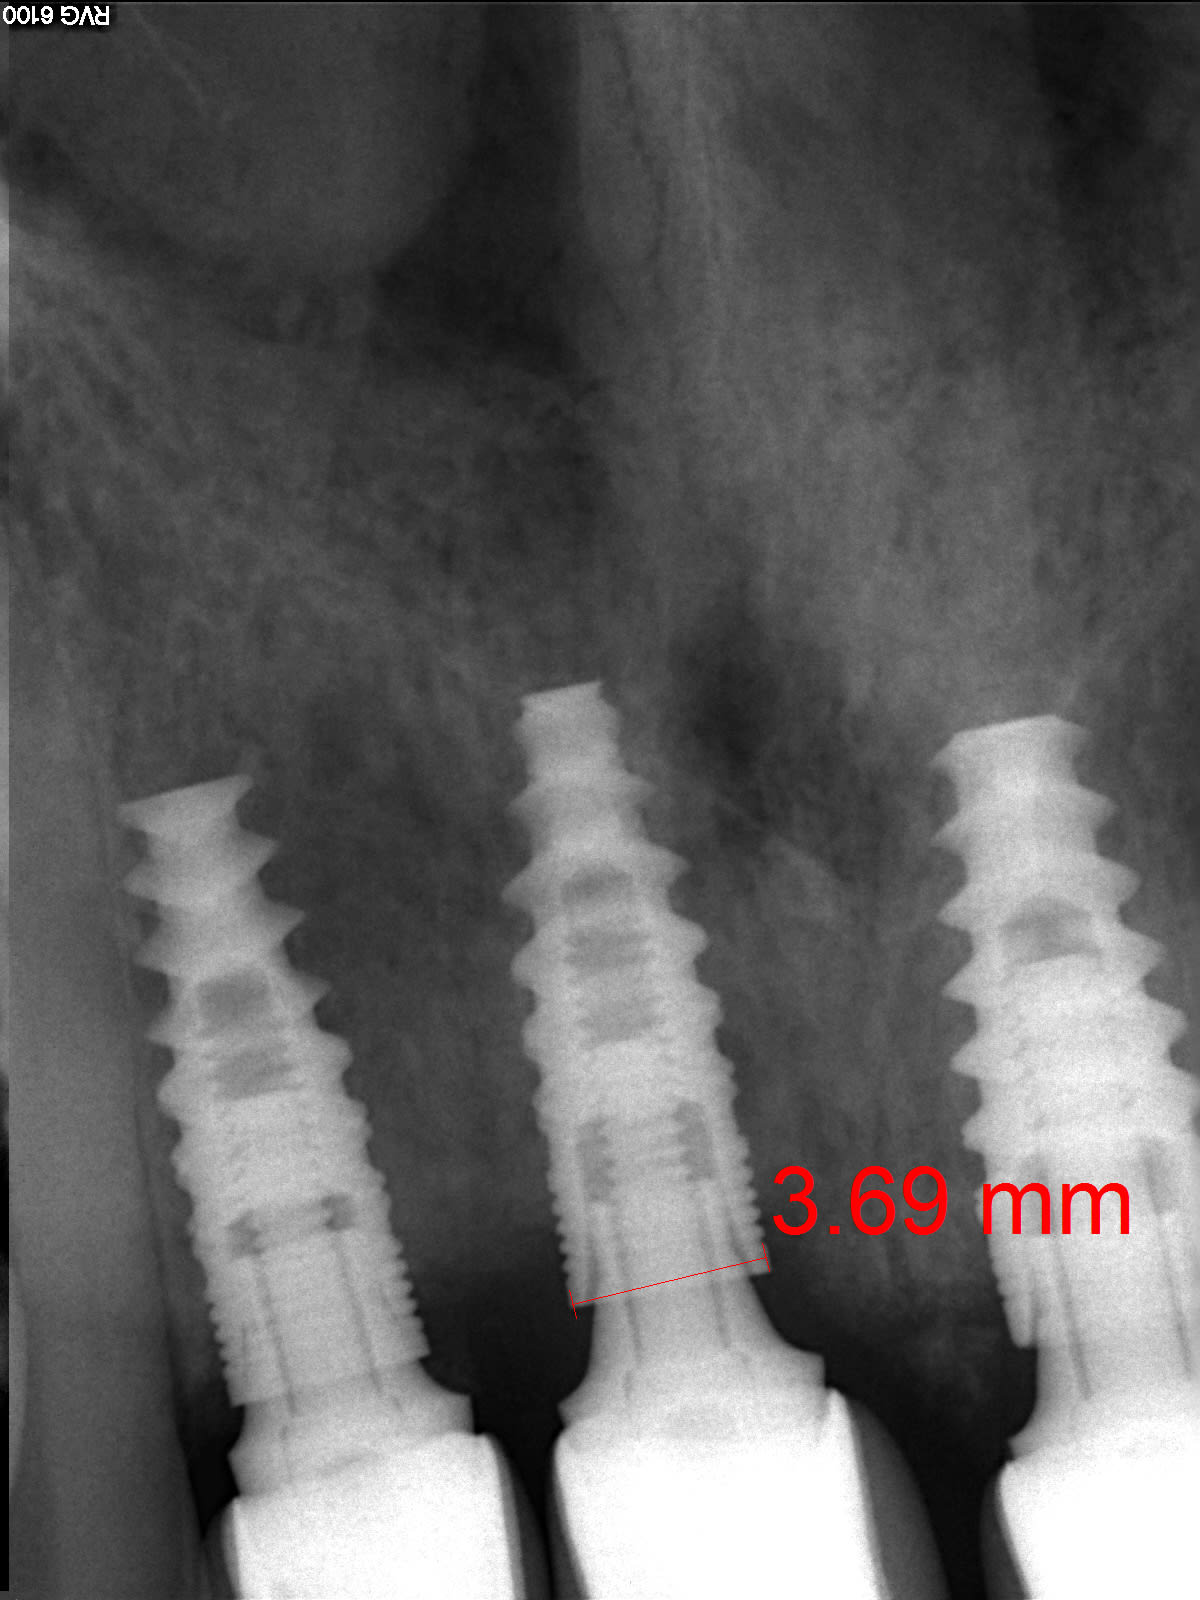

Un dentiste des USA m'a contacté pour savoir si ces implants sont de marque française. L'implant le plus distal est un Nobel Activ je pense mais les deux autres ne semblent pas être de Nobel puisqu'il y a des microfilets et non des rainures.

Vos avis s'il vous plait?

bein non c'est bien des Nobel active...

tu as l'impression que c'est des minispires à cause de l'angulation de la radio...;-)